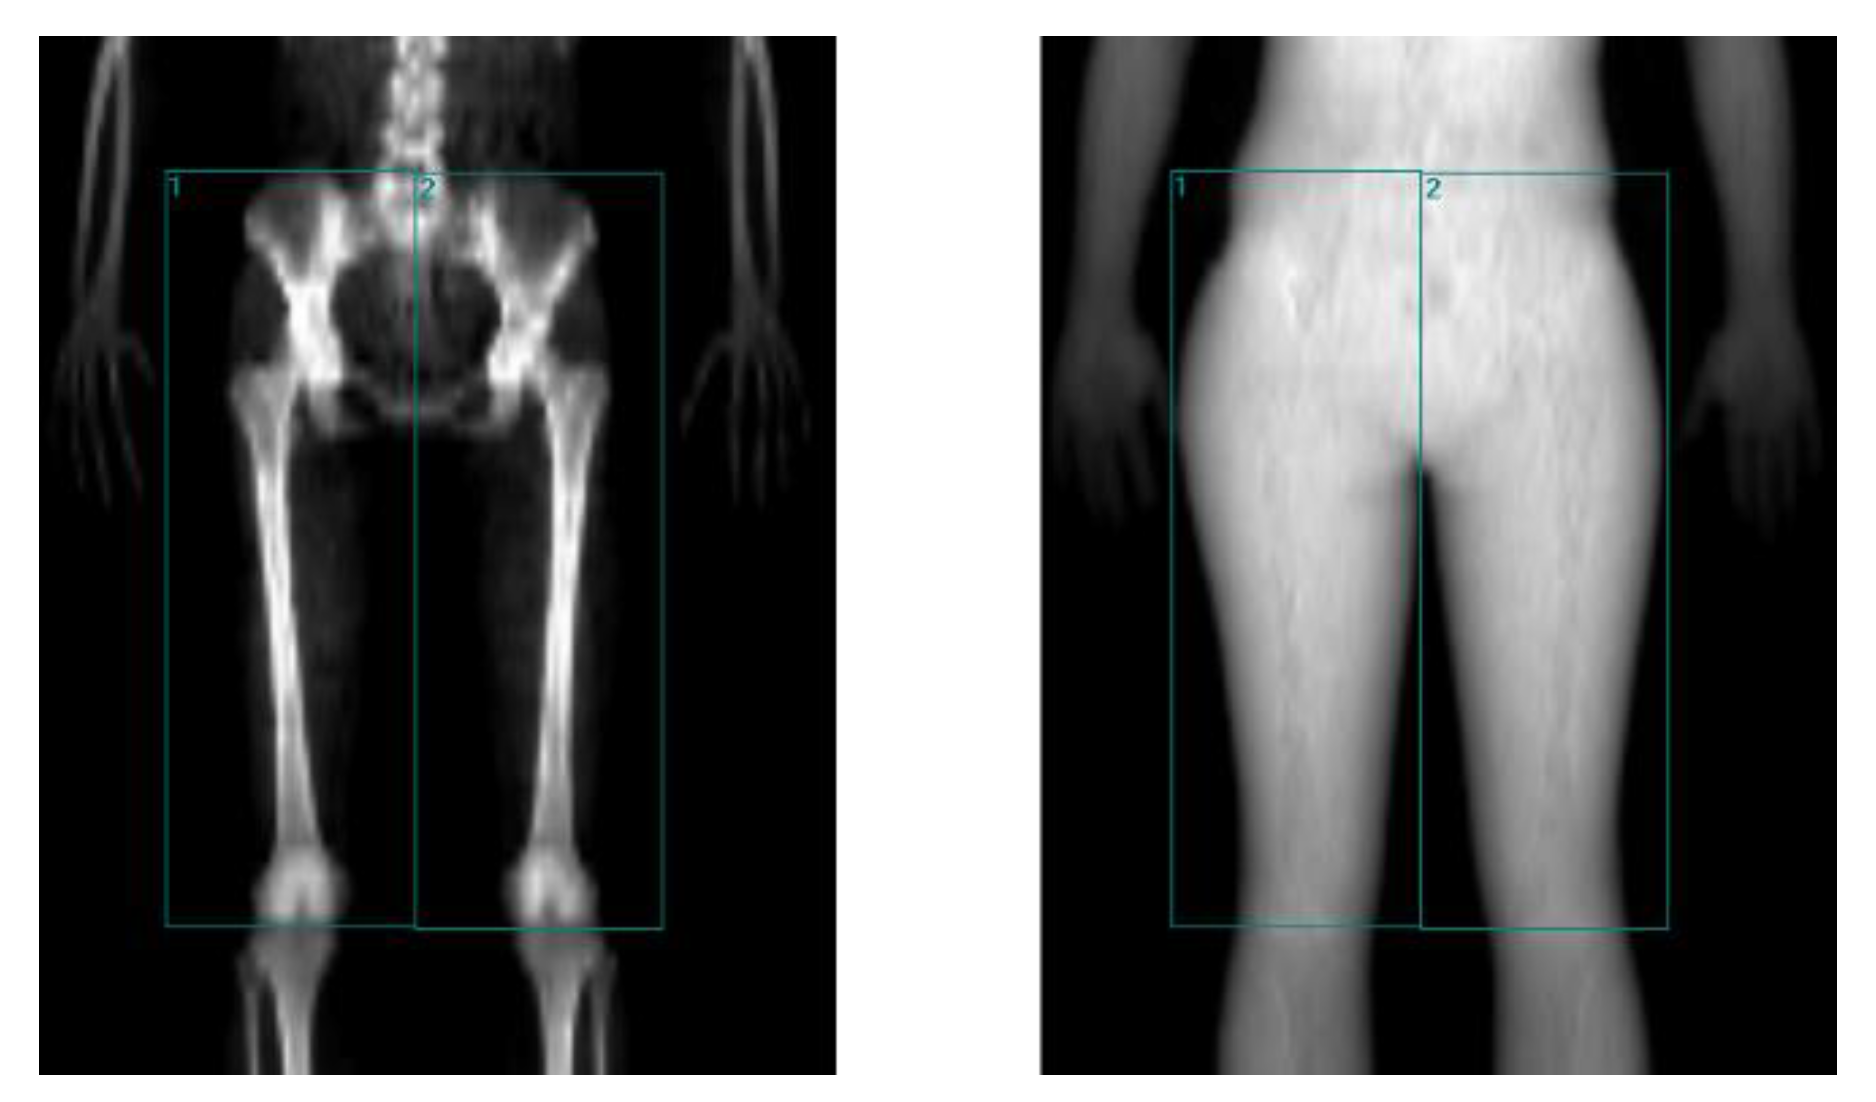

2.7. Lean Mass of the Region of Interest

Using the images generated by DXA, the lean mass of each region of interest (ROI) was determined to calculate muscle quality. The ROI was considered the region featuring most of the agonist, synergist, and antagonist muscles involved in the extension of the knees sitting at a hip angle of 110°, for which limits were determined with the following anatomical references: the superior border is delimited by the line tangent to the upper back’s radiological shadow of the iliac crests; the lower border is defined by the line that passes through the femorotibial space; the inner edge is the line perpendicular to the upper edge that runs between the two extremities; and the external border is the line outside the radiological shadow of the existing limb between the upper and lower border and perpendicular to the internal border (Figure 2).

The lean mass expressed in the Results section is the sum of the right and left ROI.

The muscle quality of patients with MS, understood as the manifested force relativized to the activated muscle mass, is an aspect little explored in the scientific literature. We collected data on the ROIs defined by DXA in studies related to muscle quality of the knee extensors in different populations without MS. Some studies determined the lean mass of the entire limb [65,66,67], while others focused on the thigh region [68,69,70]. The ROIs used in our study were limited to obtain the majority of the lean mass of the main muscle groups that intervene as agonists, synergists, antagonists, or fixators in the extension movement of the knee, with an angulation of 110° at the hip [71].